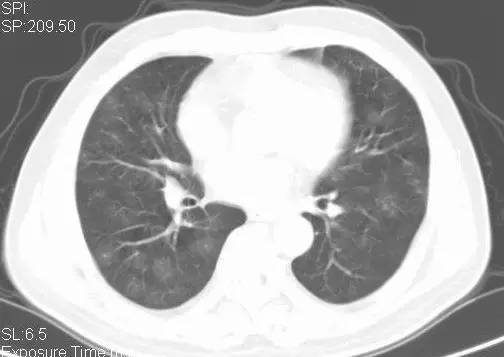

病例六(来自丁香园战友 xbfiuy 发布)

基本病史:女、13 岁,因反复咯血 8 年、再发加重 10 天入院。多次在医院治疗(止血抗炎、支气管动脉栓塞等),症状反复。10 天前再次发作并呼吸困难。既往有百日咳病史,行胸部影像学检查结果如下:

图 7 胸部 X 线显示双肺弥漫性高密度影,以右肺下叶为著

图 8 胸部 CT 显示双肺多发弥漫性小结节影及磨玻璃影,双下肺明显,右下肺融合成大片状阴影